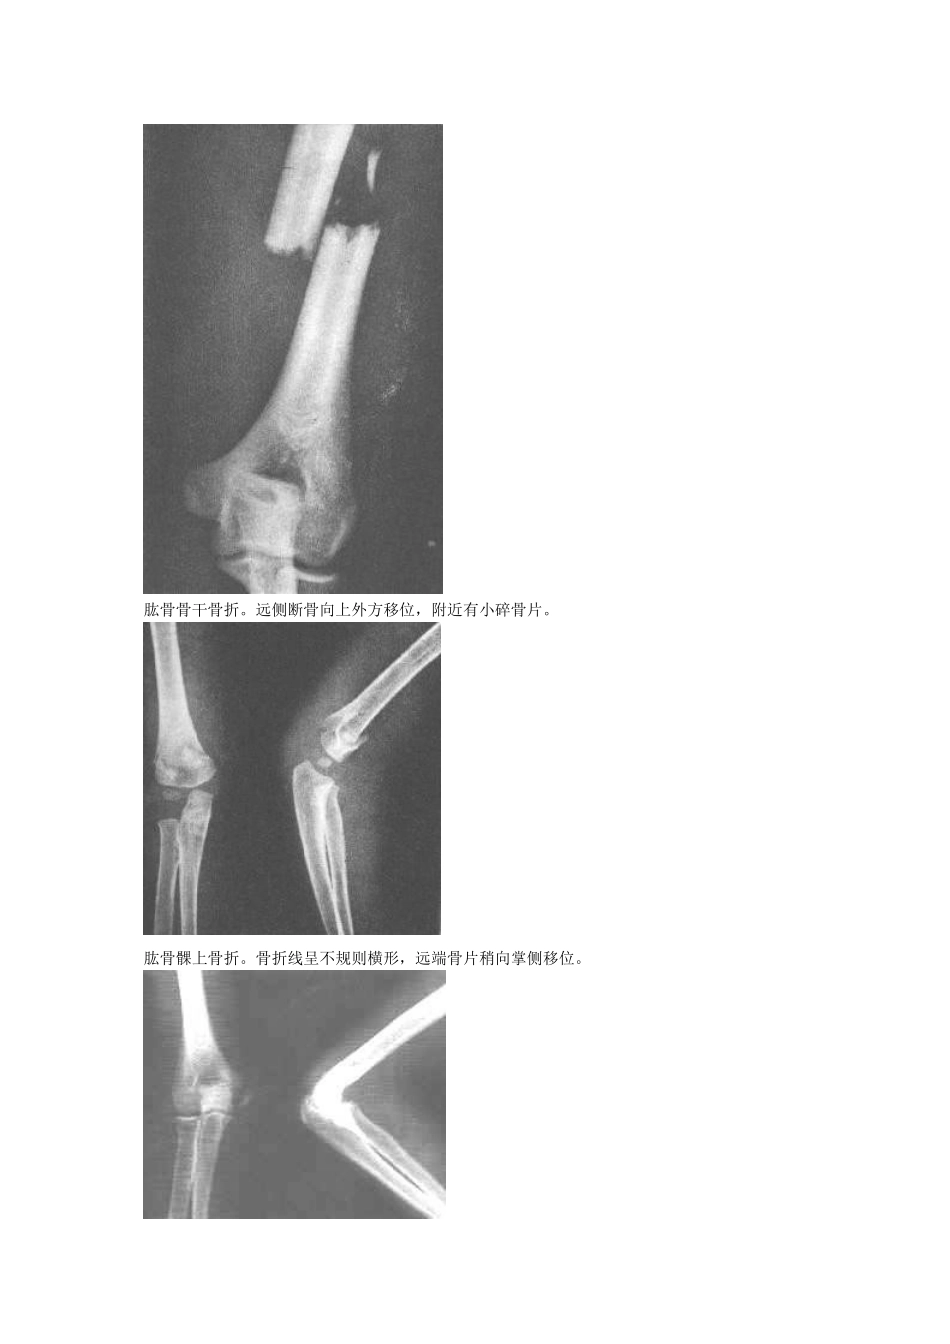

骨折图片大全!请进------锁骨骨折。锁骨骨干中段横断骨折。断端向上移位,形成凸向上之成角畸形。肩胛骨粉碎性骨折。肩胛骨外缘见一垂直形骨折线,上缘尚见星芒状骨折线。肱骨外科颈骨折(外展型)。肱骨骨干骨折。远侧断骨向上外方移位,附近有小碎骨片。肱骨髁上骨折。骨折线呈不规则横形,远端骨片稍向掌侧移位。肱骨内侧髁骨骺分离。肱骨外髁骨折。肱骨外髁骨折片向外移位并翻转。孟氏骨折(伸直型)。尺骨骨折,近侧断骨指向前方和桡侧。与远侧断骨和桡骨成角。桡骨头向前外脱位。盖氏骨折。桡骨中下1/3骨折,伴远端尺桡关节脱位和尺骨茎突骨折。柯雷氏骨折。桡骨下端横形骨折,远端断骨向背侧倾斜移位,侧位片呈“匙”样畸形,伴尺骨茎突骨折。史密斯骨折。腕舟骨骨折。腕舟骨中部可见透亮线。第一掌骨基底部骨折。下肢骨折图片股骨颈骨折腓骨下段螺旋形骨折并踝关节半脱位胫骨下段斜形骨折尾指近-中节骨粉碎性骨折并完全性脱位跟骨骨折图片